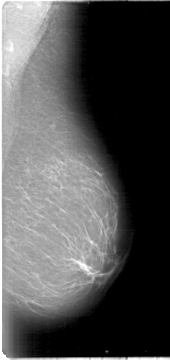

D_4009_1.LEFT_MLO

LEFT_MLO LINES 5386 PIXELS_PER_LINE 2536 BITS_PER_PIXEL 12 RESOLUTION 43.5 NON_OVERLAY